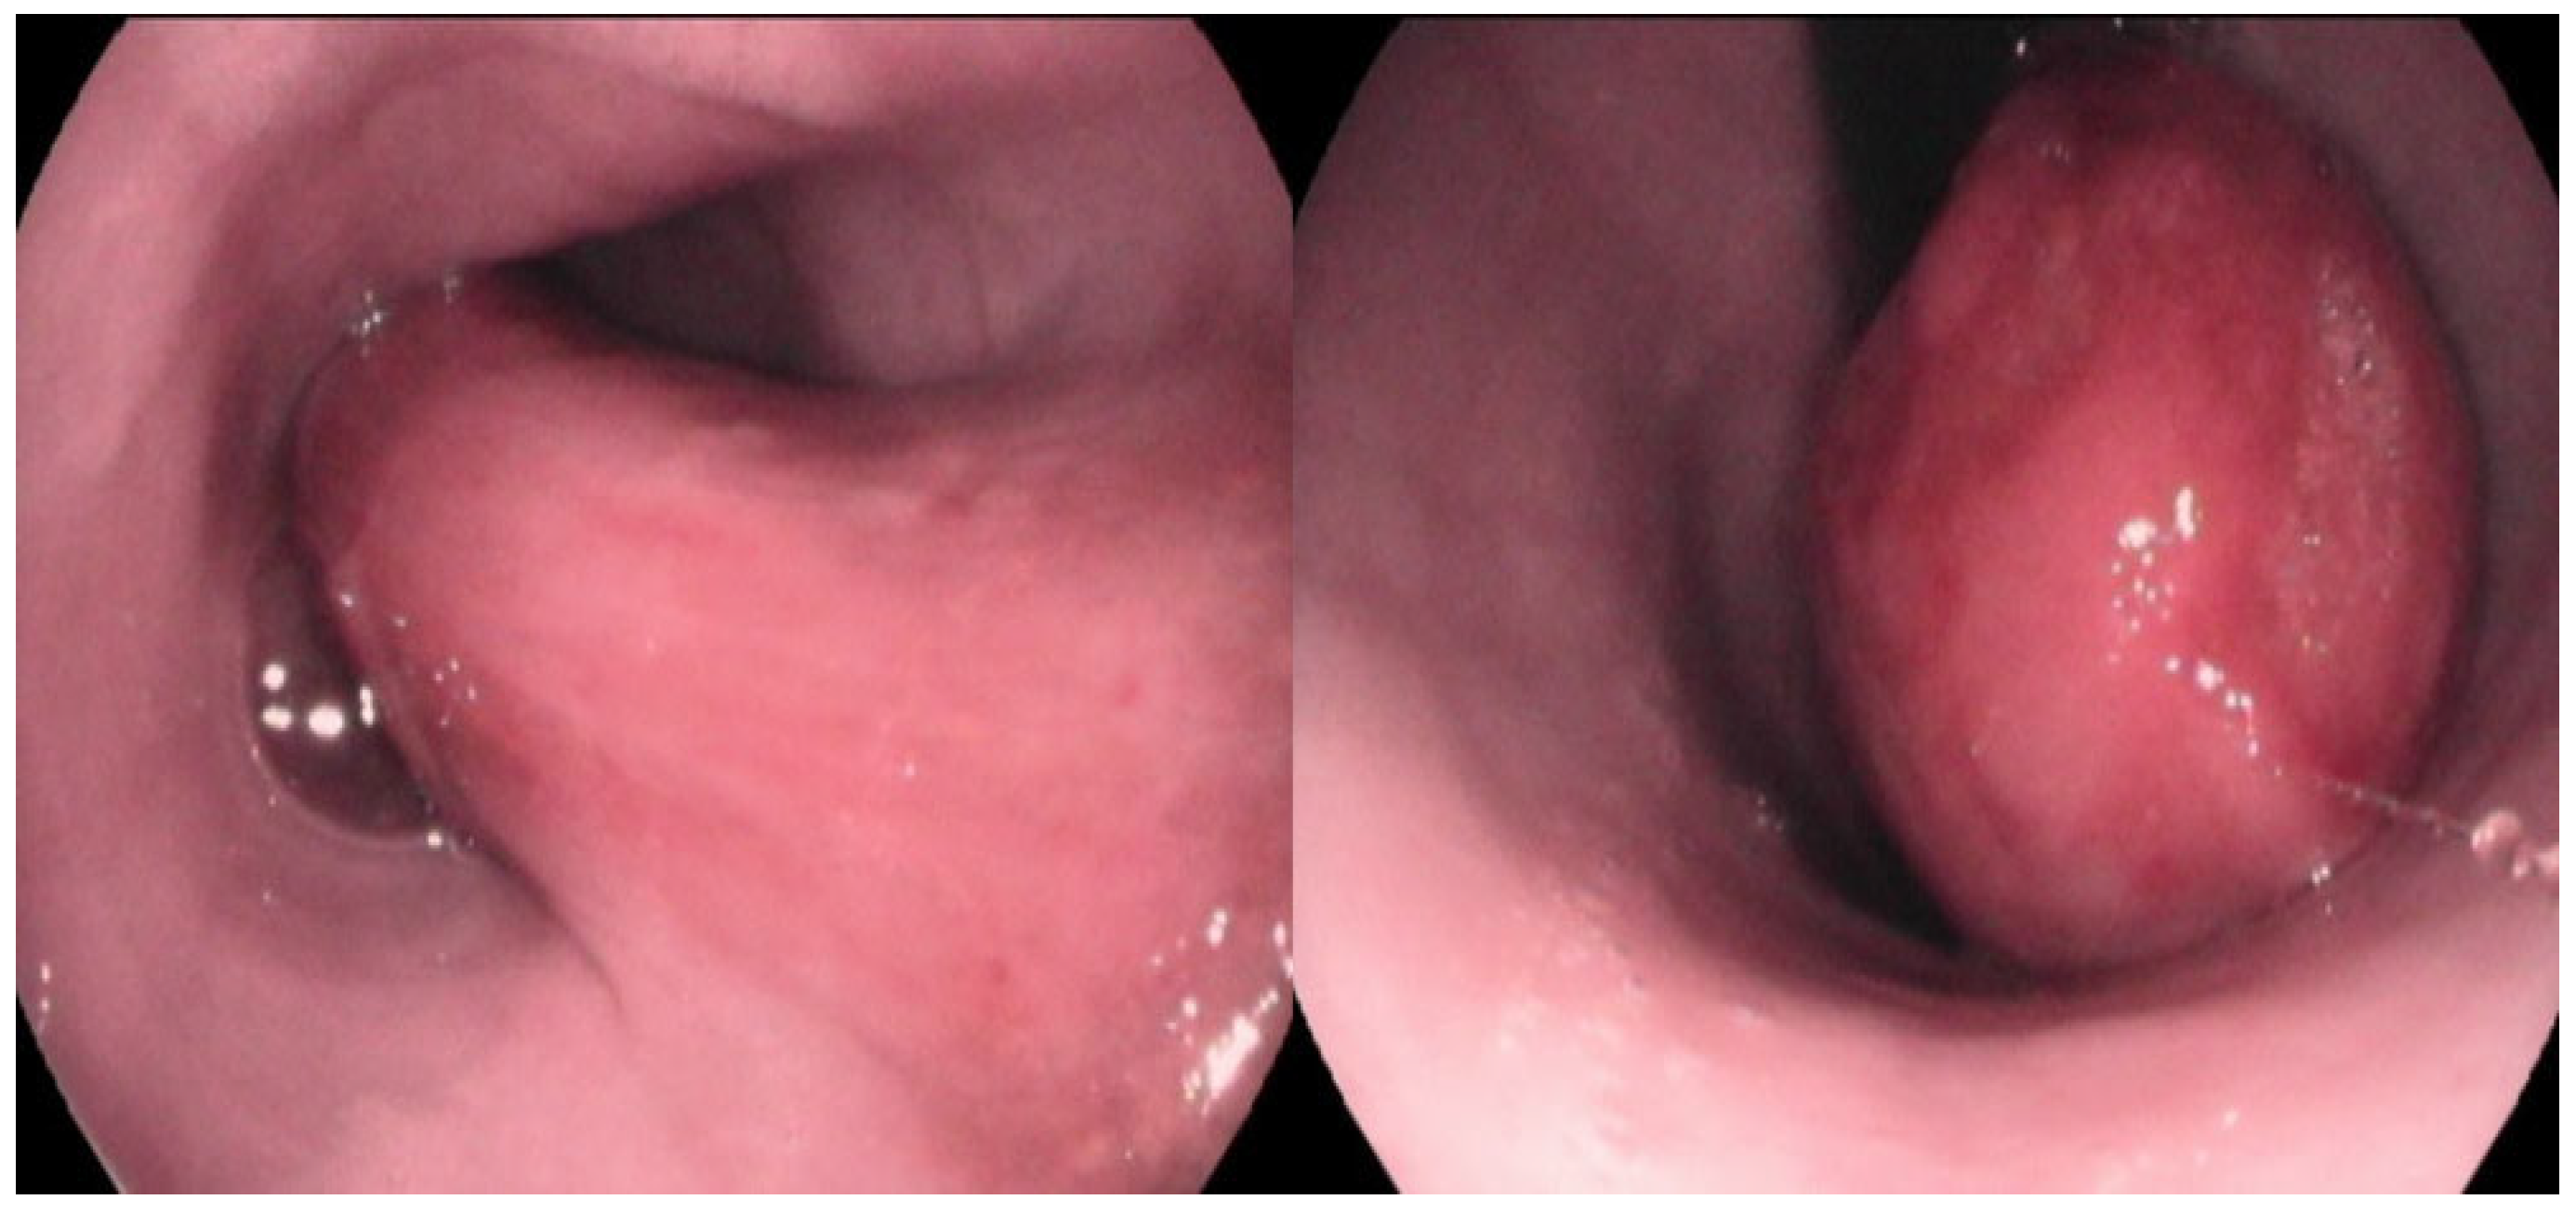

A large, highly vascular, obstructive, solitary mass with a smooth surface was detected (Figure 2). Endoscopic biopsies of the mass were collected for histopathologic examination. Specifically, seven biopsy samples from stomach, eight from duodenum, and eight from the esophageal mass were obtained using a 2.2 mm biopsy forceps. Biopsy samples were placed in 10% neutral buffered formalin and embedded in paraffin until histopathologic examination. The owner was instructed to feed the dog a high-energy, moist, home-made diet fed from an upright position to facilitate esophageal transit until histopathologic results were available.

Figure 2.

Macroscopic view of the esophageal lumen during the esophagoscopy. A large, highly vascular, obstructive, solitary mass with a smooth surface was noted. The mass was located between 1st and 7th thoracic vertebra.